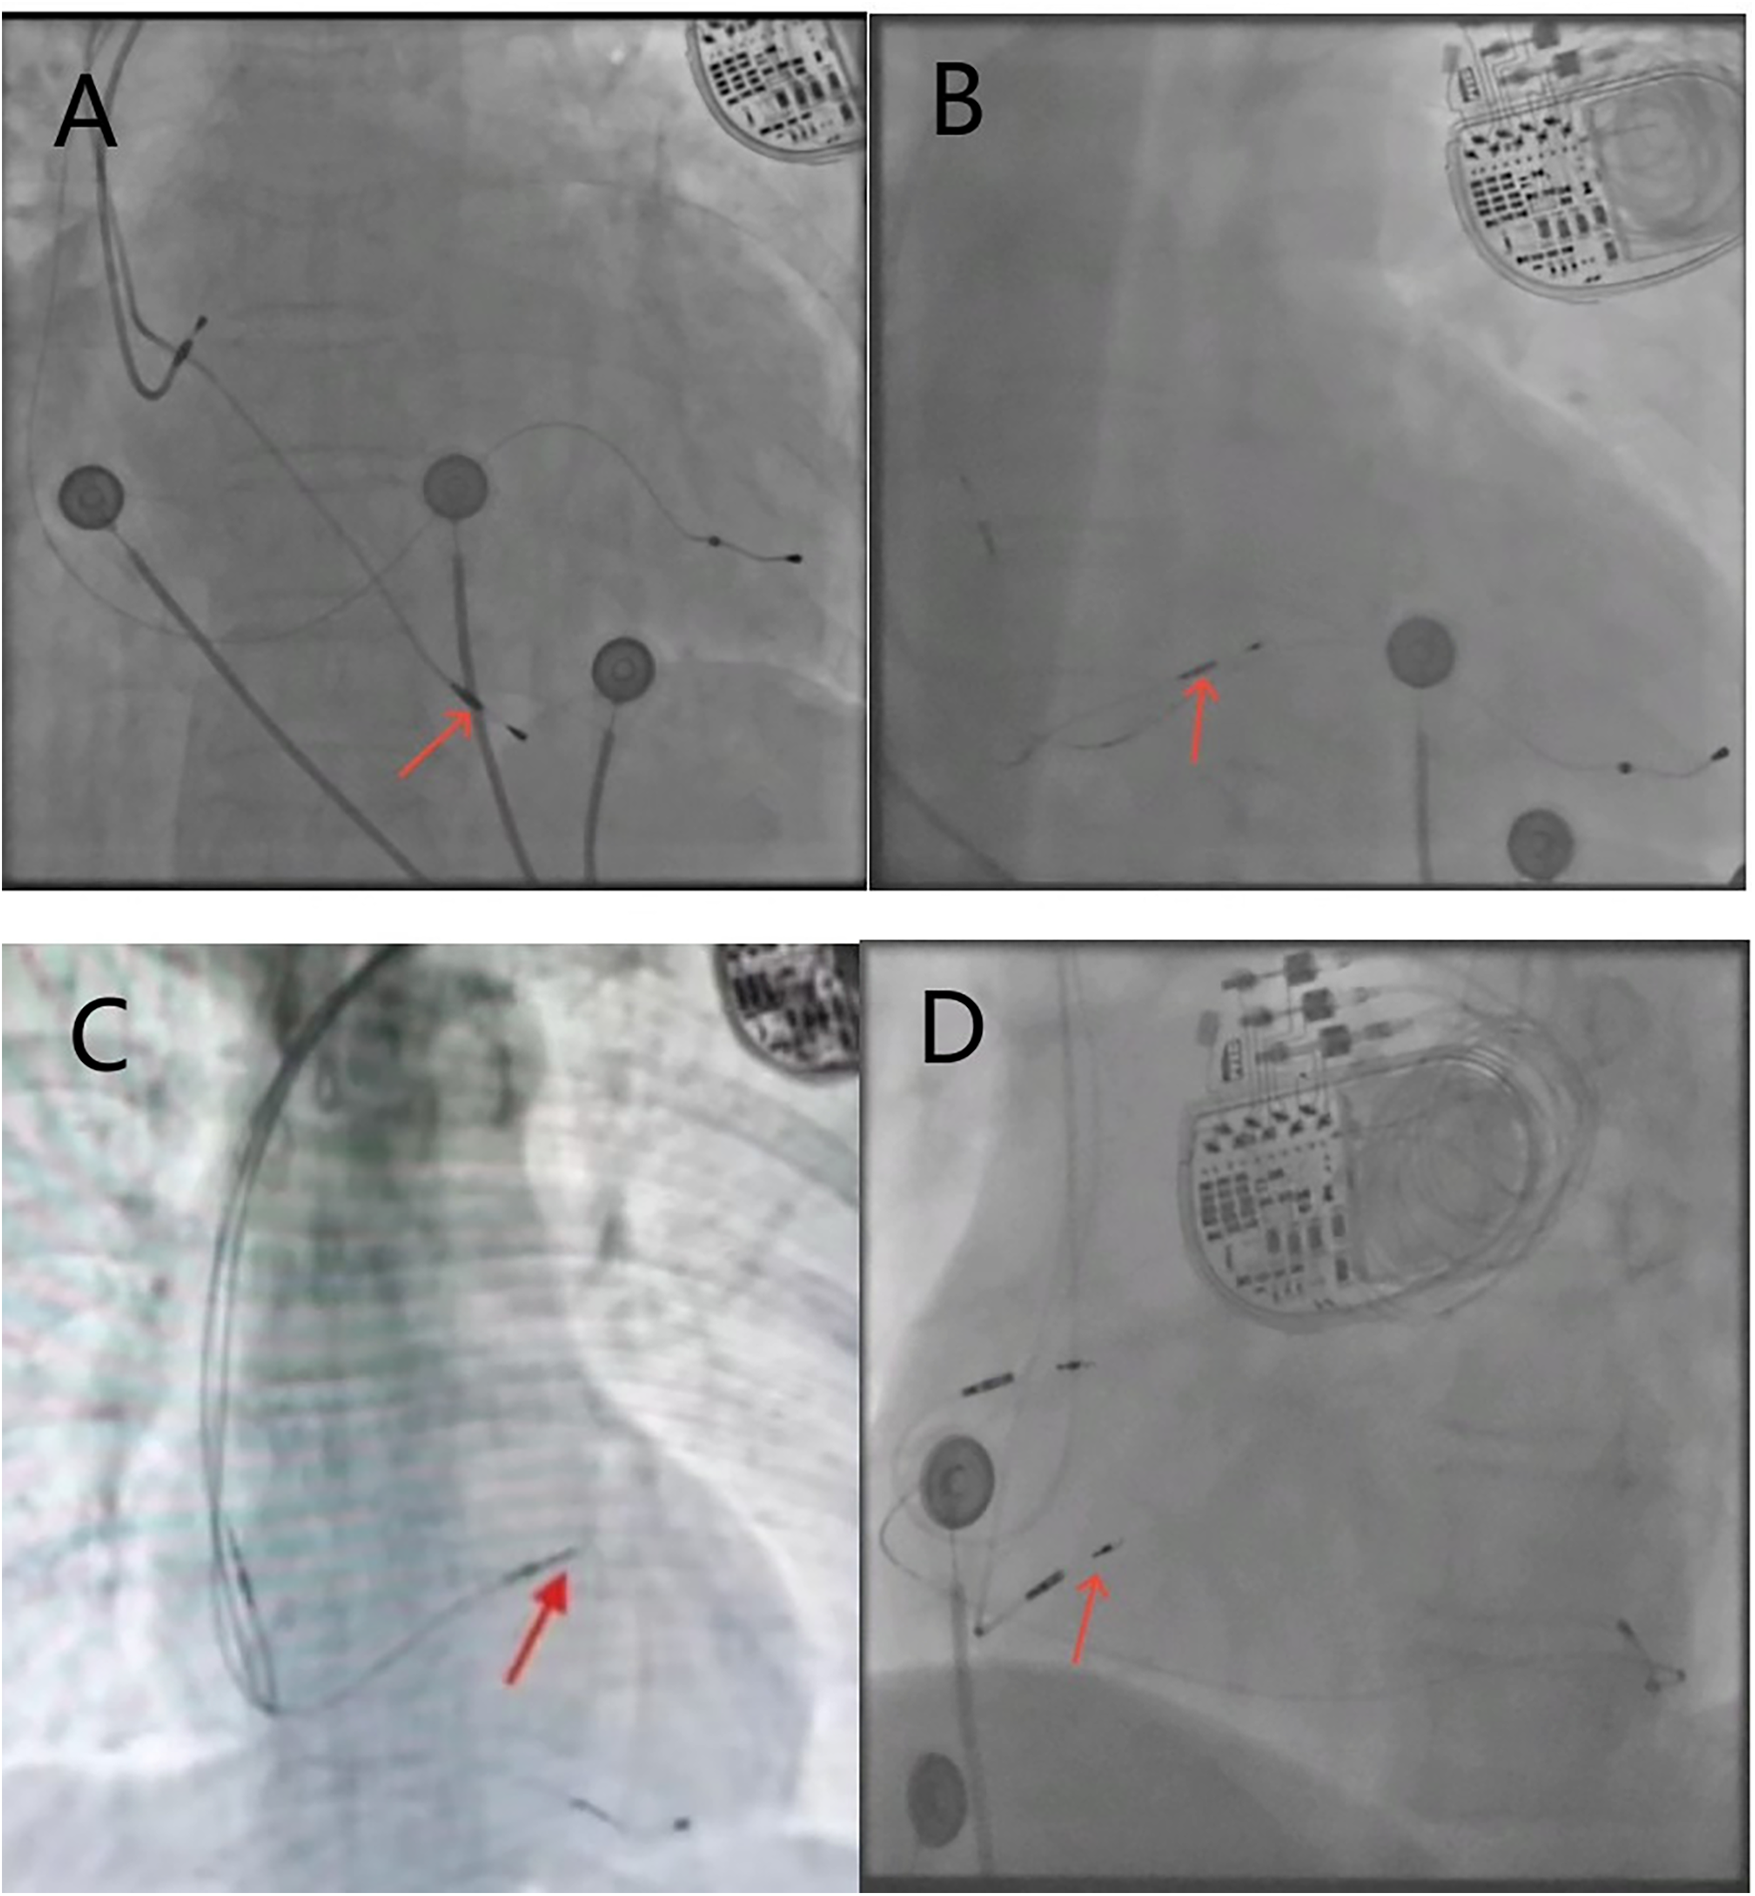

We used objective measurement criteria based on x-ray images rather than subjective anatomical description during operation to classify RV lead positions, aiming to establish a unified and repeatable classification system to minimize grouping bias. The positions of the lead in the RV septum were confirmed by the relative position of the x-ray anterior-posterior view of the heart silhouette and vertebral body shadow. The heart silhouette was divided into three regions: high, middle and low, to determine the relative height of the RV electrode tip within the heart silhouette. High-septum, the distance from the bottom of the heart silhouette is more than 2 vertebral bodies. Mid-septum, the distance from the bottom of the heart silhouette is 1.5–2 vertebral bodies. Low-septum, the distance from the bottom of the heart silhouette is less than 1.5 vertebral bodies (Figure 1).

Figure 1

X-ray fluoroscopy images of the right ventricular electrode position, with red arrows indicating the implantation site of the RV electrode. (A) Posteroanterior view of the low-septum; (B) posteroanterior view of the mid-septum; (C) posteroanterior view of the high-septum; (D) left anterior oblique view of the left bundle branch area.

Based on the left anterior oblique (LAO) view, the RV electrode was implanted into the LBBA, and the sheath tube was adjusted so that the electrode was oriented perpendicular to the ventricular septum ((Figure 1D). Right bundle branch block (RBBB) was observed during pacing, and bundle branch potential was locally recorded. The interval between pacing signal and R-wave peak in V5 or V6 remained constant and <75 ms. Local angiography showed that the tip of the electrode reached the left ventricular septal surface.